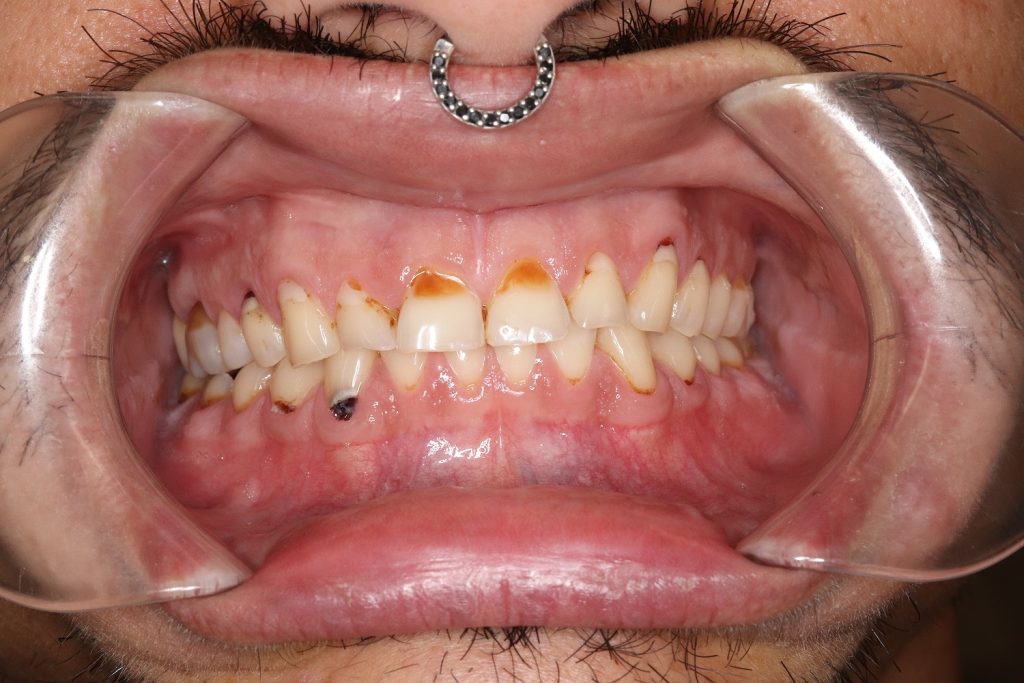

Ryan was nominated by his mother who says he is a brave, beautiful soul and always has a smile on his face despite having gone through some very challenging times. Tough circumstances beyond his control lead to him developing an eating disorder at a very young age. As well as hugely impacting on his life and wellbeing, it also took a heavy toll on his oral health.

The eating disorder has left Ryan with severely worn-down teeth – some nearly down to the nerve. Not only does this affect the appearance of the teeth but also causes extreme sensitivity. Restorative cosmetic dentistry in the form of fillings and crowns will return Ryan’s teeth to their former glory and produce a great smile – and allow him to enjoy eating, drinking and brushing without pain.

Dr Melissa Inger analysed the scans and models to develop several treatment plan options for restoring Ryan’s smile and oral health. After discussing the pros and cons of each option, Ryan opted for a combination of fillings and crowns. The fillings will fix the areas of decay and also lengthen and strengthen the back teeth, which he needs due to his worn down, short teeth.